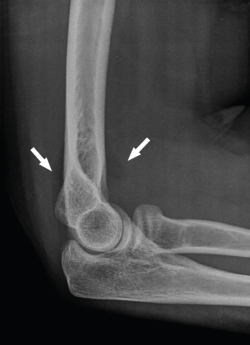

En las fracturas simples de olécranon el mecanismo típico suele ser la caída con contusión directa. En algún caso nos encontraremos con un mecanismo indirecto por tracción brusca del tríceps, pero suele darse en pacientes ancianos(29). Los patrones más complejos serán producto de lesiones de mayor energía con fuerzas rotatorias asociadas.

La clasificación más usada en las fracturas aisladas de olécranon es la de Mayo, que se basa en 3 factores: desplazamiento de la fractura, presencia de conminución y estabilidad de la articulación humerocubital (subluxación). Es una clasificación simple pero está correlacionada con la severidad de las lesiones y con la elección del tratamiento (Tabla 3)(30).

- 2A/2B: son las más frecuentes. La técnica de elección en las fracturas simples en 2 partes es un cerclaje de alambre (obenque) sobre 2 agujas de Kirschner (AK) ancladas a la cortical anterior o colocadas intramedulares. En el primer caso, tenemos riesgo de lesionar las estructuras neurovasculares volares, por lo que no deben sobresalir más de 10 mm; en el segundo caso, el riesgo de que migren proximalmente es mayor(34,35). Se pensó que con este montaje las fuerzas de tensión se transforman en fuerzas de compresión, pero varios estudios realizados no han podido demostrar este principio(36). En las conminutas 2B se recomienda fijación con placa, precisamente para evitar la excesiva comprensión de la cavidad sigmoidea que llevaría a una artrosis precoz. Se recomiendan las placas premoldeadas LCP (locking compression plate). Su efectividad y seguridad están de sobra probadas; sin embargo, al ir en una posición dorsal y ser el cúbito subcutáneo, pueden producir irritación de los tejidos blandos y con cierta frecuencia hay que retirarlas. Aun así, el índice de retirada es mucho mayor en los cerclajes, que puede llegar hasta el 90%(37,38). La alternativa es usar 2 placas laterales de bajo perfil colocadas a ambos lados de la cresta, una medial y otra lateral, que además tienen la ventaja de permitir una fijación bicortical de los fragmentos más proximales. En cualquier caso, los estudios demuestran que ambos métodos tienen buenos resultados y no existen diferencias a corto plazo. Últimamente, se están publicando modificaciones a la técnica clásica del obenque, usando una sutura trenzada de alta resistencia en lugar de alambre(39). En este caso solo tendríamos que retirar las AK y este es un proceso mucho menos invasivo (Figura 8).

Figura 8. Ejemplos de fracturas de olécranon en 2 partes (tipo 2A) fijadas con obenque (A y B) y fracturas de tipo 2B fijadas con distintos diseños de placas (C y D).